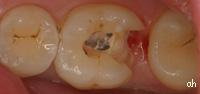

molaire avec une ancienne obturation déféctueuse

après ablation de la vieille obturation

nouveau composite en place